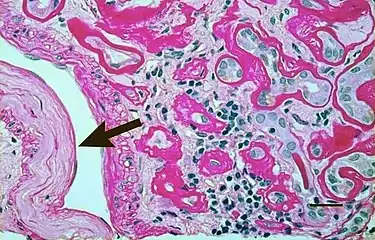

Light micrograph showing signs of hypertensive nephropathy: interstitial fibrosis, tubular atrophy with thickened tubular basement membranes, and fibrous intimal thickening of a small artery (arrow).

Histology

In benign nephrosclerosis, the changes occurring are gradual and progressive, however, there can be sufficient kidney reserve capacity to maintain adequate kidney function for many years.[10] The large renal arteries exhibit intimal thickening, medial hypertrophy, duplication of the elastic layer. The changes in small arterioles include hyaline arteriolosclerosis (deposition of hyaline, collagenous material), which causes glomerular collapse (wrinkling and thickening of capillary basement membranes and collapse of capillary lumen) and solidification (glomeruli exhibit sclerosis and increase in mesangial matrix). The degree of scarring correlates with the degree of glomerular filtration deficit.